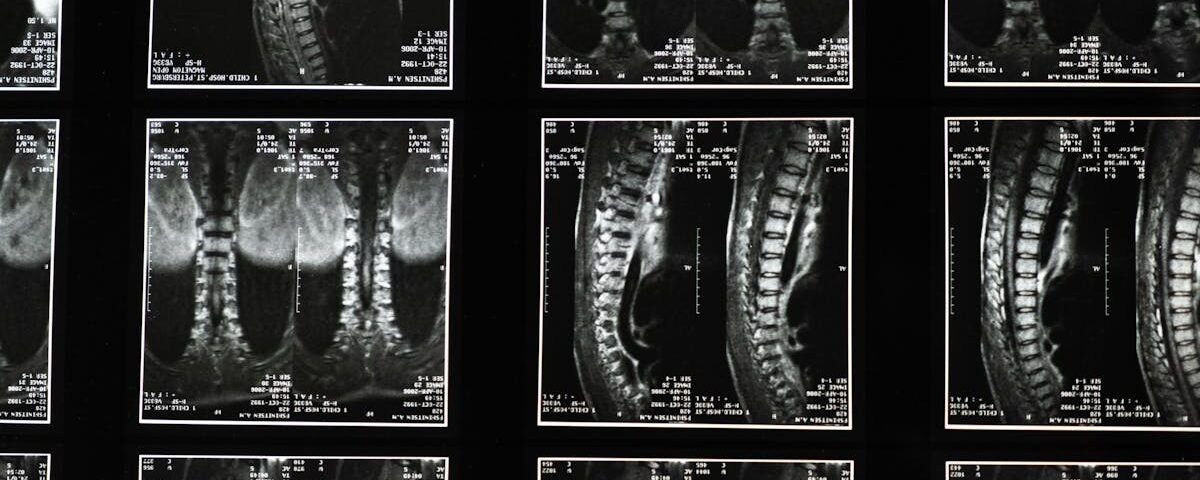

Ce podcast médical décrit les bombements et hernies discales, distinguant ces affections selon la gravité de la dégénérescence discale. Il détaille leurs causes, symptômes, diagnostics (souvent […]

La décompression spinale est une technique thérapeutique visant à soulager les douleurs liées aux affections de la colonne vertébrale. Elle s’adresse à ceux qui rencontrent des problèmes comme la hernie discale, le bombement discal ou la sténose spinale. En utilisant des méthodes non invasives, cette approche vise à réduire la pression sur les disques intervertébraux, favorisant ainsi la circulation sanguine et le processus de guérison dans la région du dos.

La décompression spinale est une méthode thérapeutique qui répond à des pathologies variées liées à la colonne vertébrale, notamment les troubles tels que les hernies discales, les bombements discaux et les sténoses spinales. Ces conditions peuvent entraîner des douleurs aiguës et chroniques, ainsi qu’une diminution de la qualité de vie. Grâce à une approche personnalisée, la décompression spinale s’adapte aux besoins spécifiques de chaque patient, vis-à-vis des douleurs qu’il ressent.